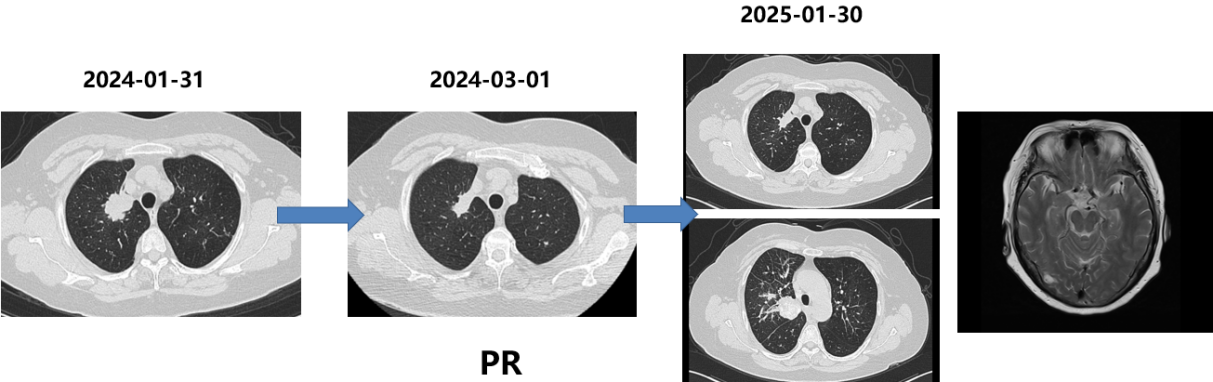

三线治疗(2024-01至2025-01)

依据:再次活检仍提示腺癌且EGFR 19del阳性,考虑EGFR-TKI再挑战。

方案:

药物:阿美替尼110mg QD。

胸部CT和脑MRI(2025-01-30):肺部病灶进展,右侧脑转移病灶。

局部治疗放疗(2025-01-30开始):

右侧脑转移灶:SRT,PTV D95/30Gy/5F。

肺部病灶及纵隔淋巴引流区:IMRT(调强放疗),PGTV 60Gy,PTV 54Gy/30F。

胸部CT(2025-03-15):肺部病灶明显增大,实变范围扩大。

四次活检病理:小细胞神经内分泌癌。